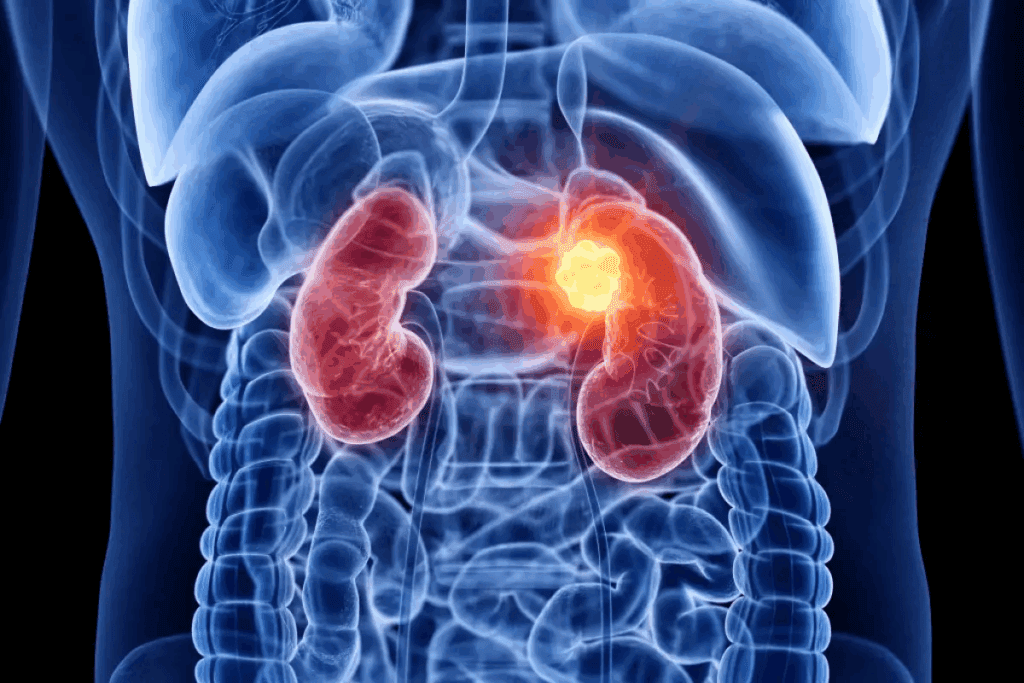

Renal cell carcinoma (RCC) is the most common kidney cancer. It’s a complex challenge with many treatment approaches. These are based on tumor characteristics and patient factors. Explore 7 effective kidney tumor treatment options. Our guide covers the latest therapies for RCC, from surgery to ablation.

When kidney cells grow out of control, kidney cancer develops. Symptoms include flank pain, high blood pressure, and blood in urine.

Understanding Kidney Tumors and Renal Cell Carcinoma

Risk Factors and Prevalence

Several things can increase your risk of renal cell carcinoma. These include smoking, being overweight, high blood pressure, and some genetic conditions. Knowing these risks helps prevent and catch cancer early.

Men are more likely to get this cancer than women. It usually happens to people between 50 and 70 years old.